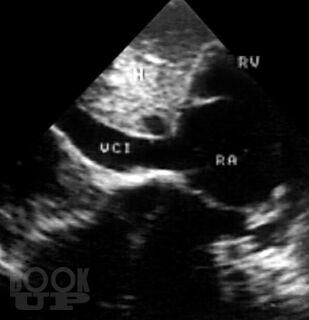

В атласе на большом числе богато иллюстрированных примеров дана эхо- и допплеркардиографическая картина врожденных пороков и ряда заболеваний сердца, а также правила применения методики ультразвукового исследования. Издание восполняет дефицит информации об ультразвуковой диагностике многих сложных врожденных пороков сердца и возможности оценки состояния больных после хирургической коррекции порока.

При подготовке атласа сотрудниками Научного центра сердечно-сосудистой хирургии им. А.Н. Бакулева РАМН (директор – академик РАМН Л.А. Бокерия) использован опыт ультразвукового исследования больных с пороками и заболеваниями сердца (более 60000 пациентов), обследованных в Центре за период с 1976 по 2003 г.